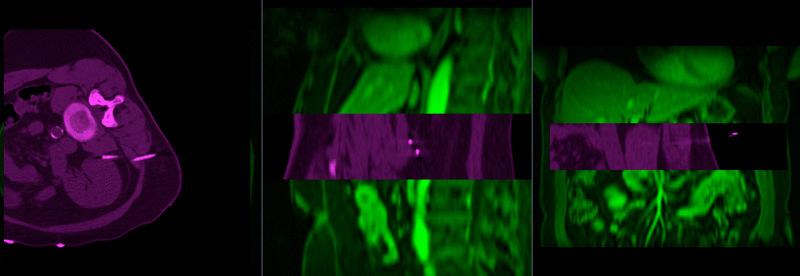

File:RegLib C17 unregistered.gif

Size of this preview: 800 × 276 pixels. Other resolutions: 320 × 110 pixels | 838 × 289 pixels.

Original file (838 × 289 pixels, file size: 232 KB, MIME type: image/gif, looped, 2 frames, 1.0 s)